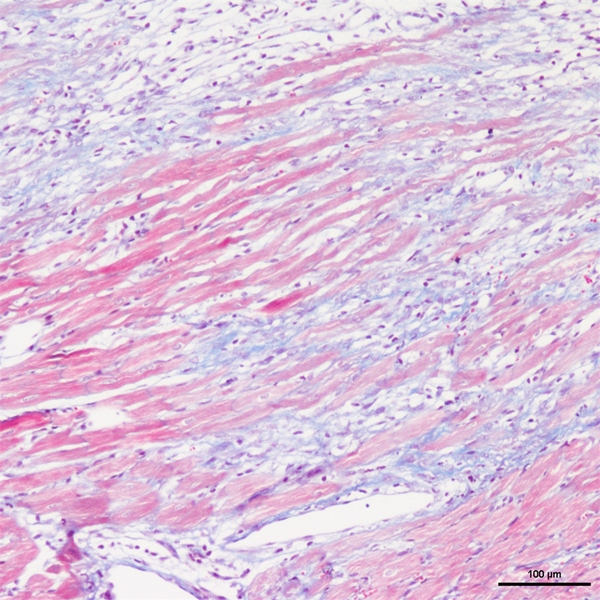

Masson染色

丽春红酸性品红-苯胺蓝染色,是用于检测动物组织中胶原纤维的一种染色方法之一,能够将胶原纤维染成蓝色,肌纤维、和红细胞呈红色,可用于鉴胶原纤维和肌纤维;并显示各种组织胶原纤维含量及纤维化程度。

Masson染色时胶原纤维呈蓝色(被苯胺蓝所染)或绿色(被亮绿所染),肌纤维呈红色(被酸性品红和丽春红所染),这与阴离子染料分子的大小和组织的渗透性有关。如已固定的组织用一系列阴离子水溶性染料先后或混合染色,则可发现红细胞被最小分子的阴离子染料着染,肌纤维与胞质被中等大小的阴离子染料着染,而胶原纤维则被大分子的阴离子染料着染。由此说明了红细胞对阴离子染料的渗透性最小,肌纤维与胞质次之,而胶原纤维具有最大的渗透性。根据组织不同的渗透性能,选择分子大小不同的阴离子染料进行染色,便可把不同组织成分显示出来。

实验结果展示:

<masson-心梗>